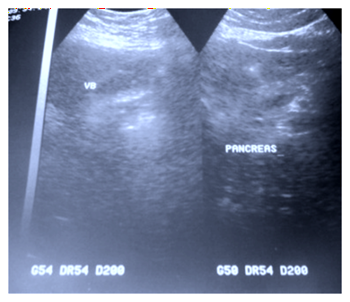

The biological assessment showed an elevation of crp to 48 mg/l. There was no hyperleukocytosis or anemia, cholestasis or cytolysis, hepatitis b, hepatitis c and hiv serologies were negative. The abdominal ultrasound performed revealed a thin-walled vesicle containing several mini-stones (figure 1).

Figure 1. Abdominal ultrasound showing a

vesicle with small stones.